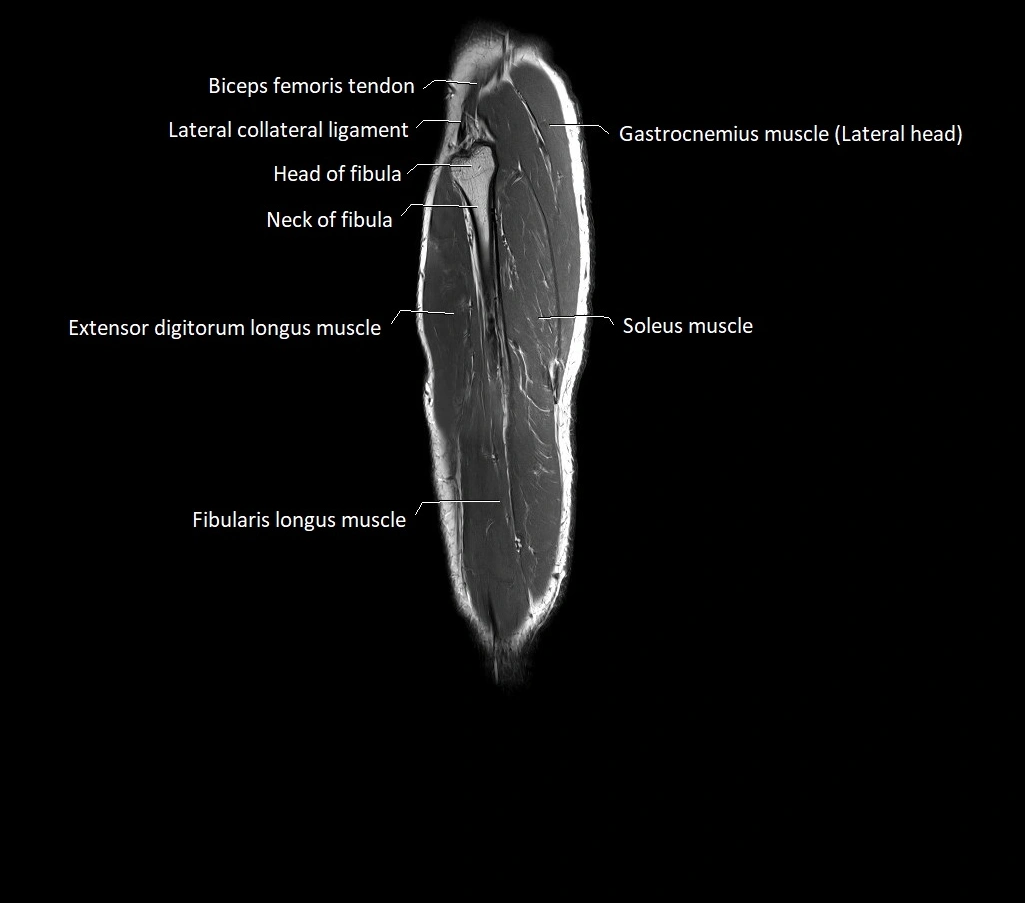

MRI image